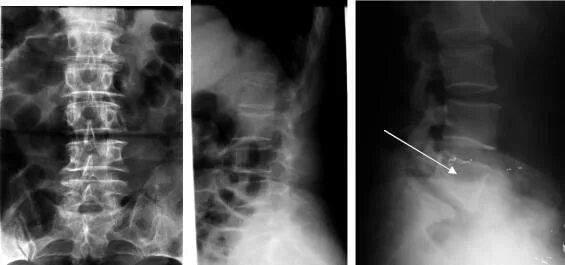

Склероз замыкательных пластинок позвоночника рентген. замыкательные пластинки тел позвонков на рентген. остеосклероз позвоночника рентген. замыкательные пластинки склерозированы шейного отдела.

Склероз замыкательных пластинок позвоночника рентген. замыкательные пластинки тел позвонков на рентген. замыкательные пластинки позвонков склерозированы. склероз замыкательных пластин позвоночника что это.

Остеосклероз позвоночника рентген. замыкательные пластинки тел позвонков на рентген. перифокальный остеосклероз. субхондральный склероз пограничных замыкательных пластинок.

Замыкательные пластинки тел позвонков на рентген. замыкательные пластинки склерозированы шейного отдела. субхондральный склероз тела s1. склероз замыкательных пластинок позвоночника рентген.

Склерозированы замыкательные пластины тел позвонков. рентген поясничного отдела с остеохондрозом 1 степени. рентгенологическая классификация остеохондроза. склероз смежных замыкательных пластинок тел позвонков.